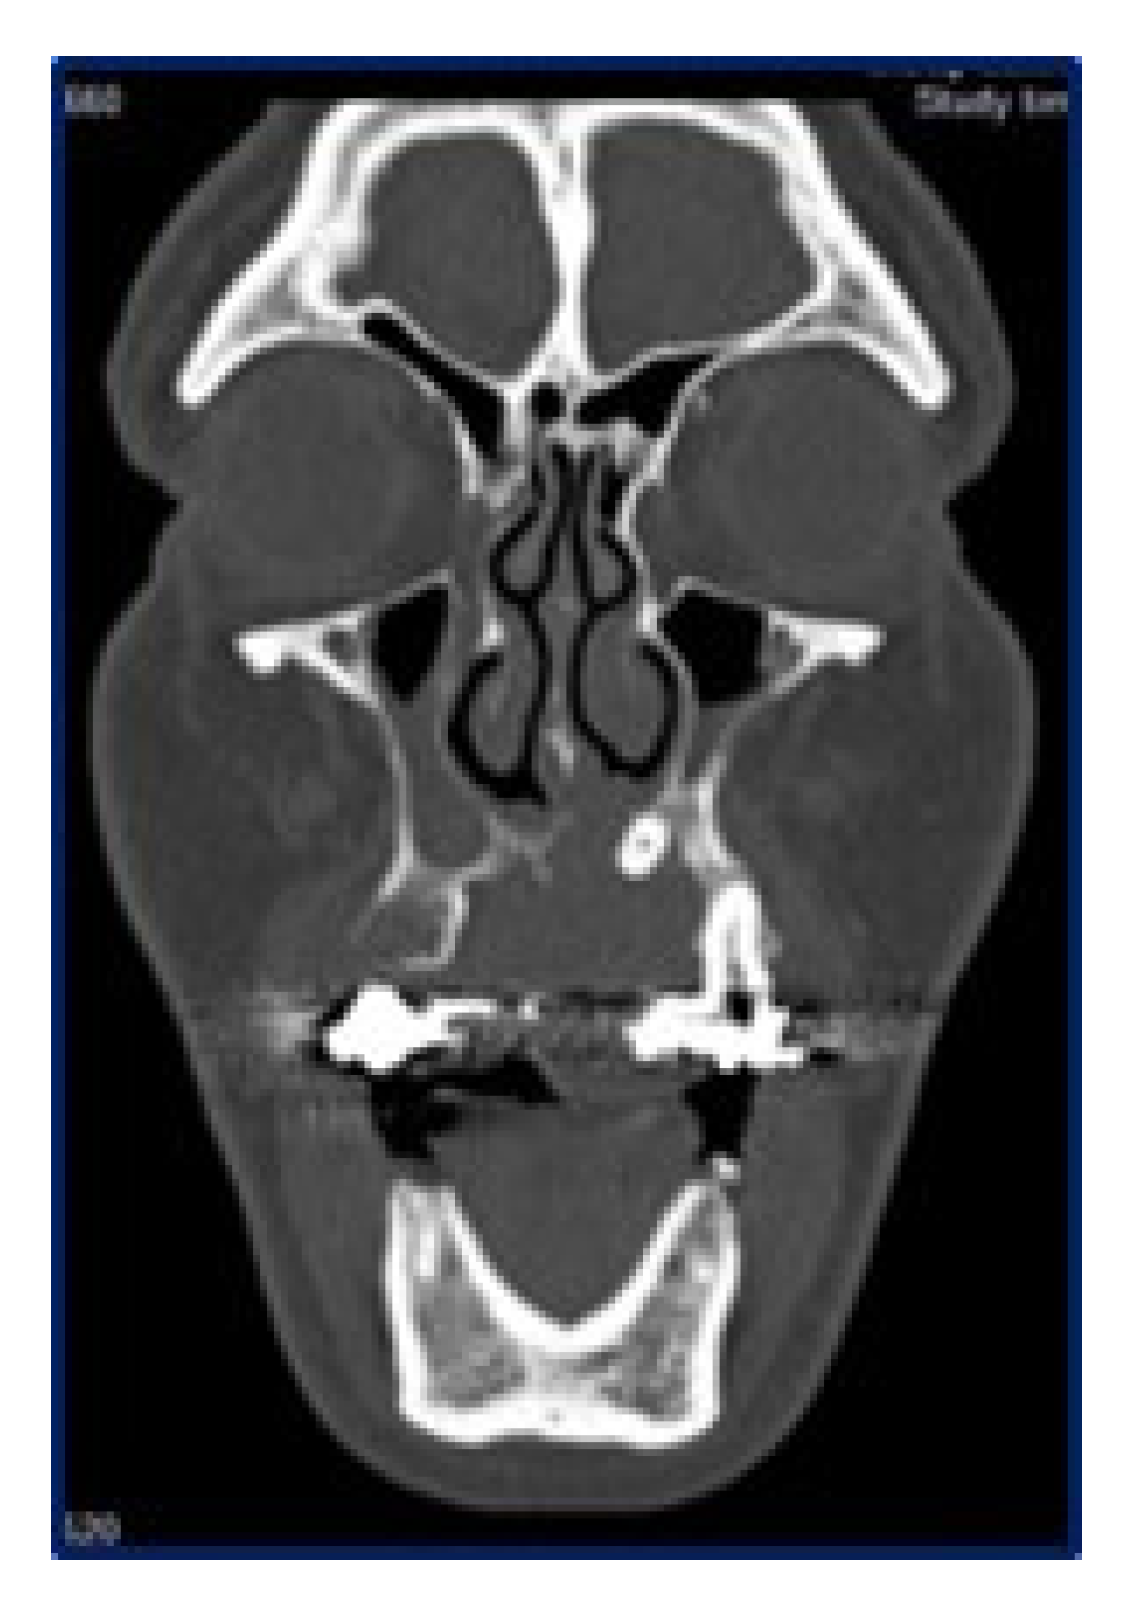

Panoramic radiograms (Figure 2) and CT-scans (Figure 3) highlighted maxillary and palatal bone involvement, while US and MRI of the head and neck were negative for relevant loco-regional lymphadenopathy. A PET scan, brain CT and abdominal US showed no metastatic deposits. On such bases, the diagnostic hypothesis was of primary oral MM, clinically staged as T4aN0M0 [6].

Figure 3.

Sagittal computed tomography showing the extension of the lesion, with erosion of the hard palate and involvement of the maxillary sinus up to the orbital base.